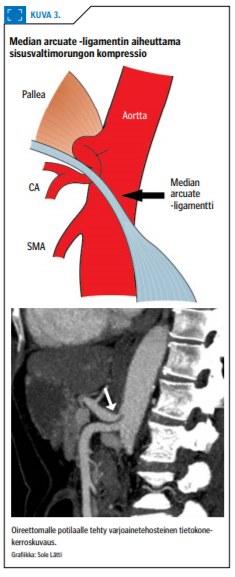

MALS on hyvin harvinainen ylävatsakivun aiheuttaja, eikä tarkkaa kivun mekanismia tunneta. Median arcuate -ligamentti (ligamentum arcuatum mediale) on pallean fibroottinen ja kaarimainen, aortan yli menevä silta, joka yhdistää vasemman ja oikean palleapilarin.

Noin kolmasosalla ihmisistä sisusvaltimorungon lähtökohta on tämän ligamentin yläpuolella, jolloin valtimo voi puristua ligamentin alla etenkin maksimaalisen uloshengityksen aikana (kuva «»3). Median arcuate -ligamentin aiheuttamaa sisusvaltimorungon ulkoista kompressiota esiintyy sattumalöydöksenä tietokonekerroskuvantamisessa noin 3 %:lla vatsan suhteen oireettomista potilaista. Silloin harvoin, kun kompressio aiheuttaa vatsaoireita, puhutaan varsinaisesta oireyhtymästä eli MALS:sta. Oireiden arvellaan johtuvan poikkeavasta verenvirtauksesta ylävatsan alueella ja ligamentin aiheuttamasta sisuspunoksen (celiac ganglion) hermokompressiosta (1,16).